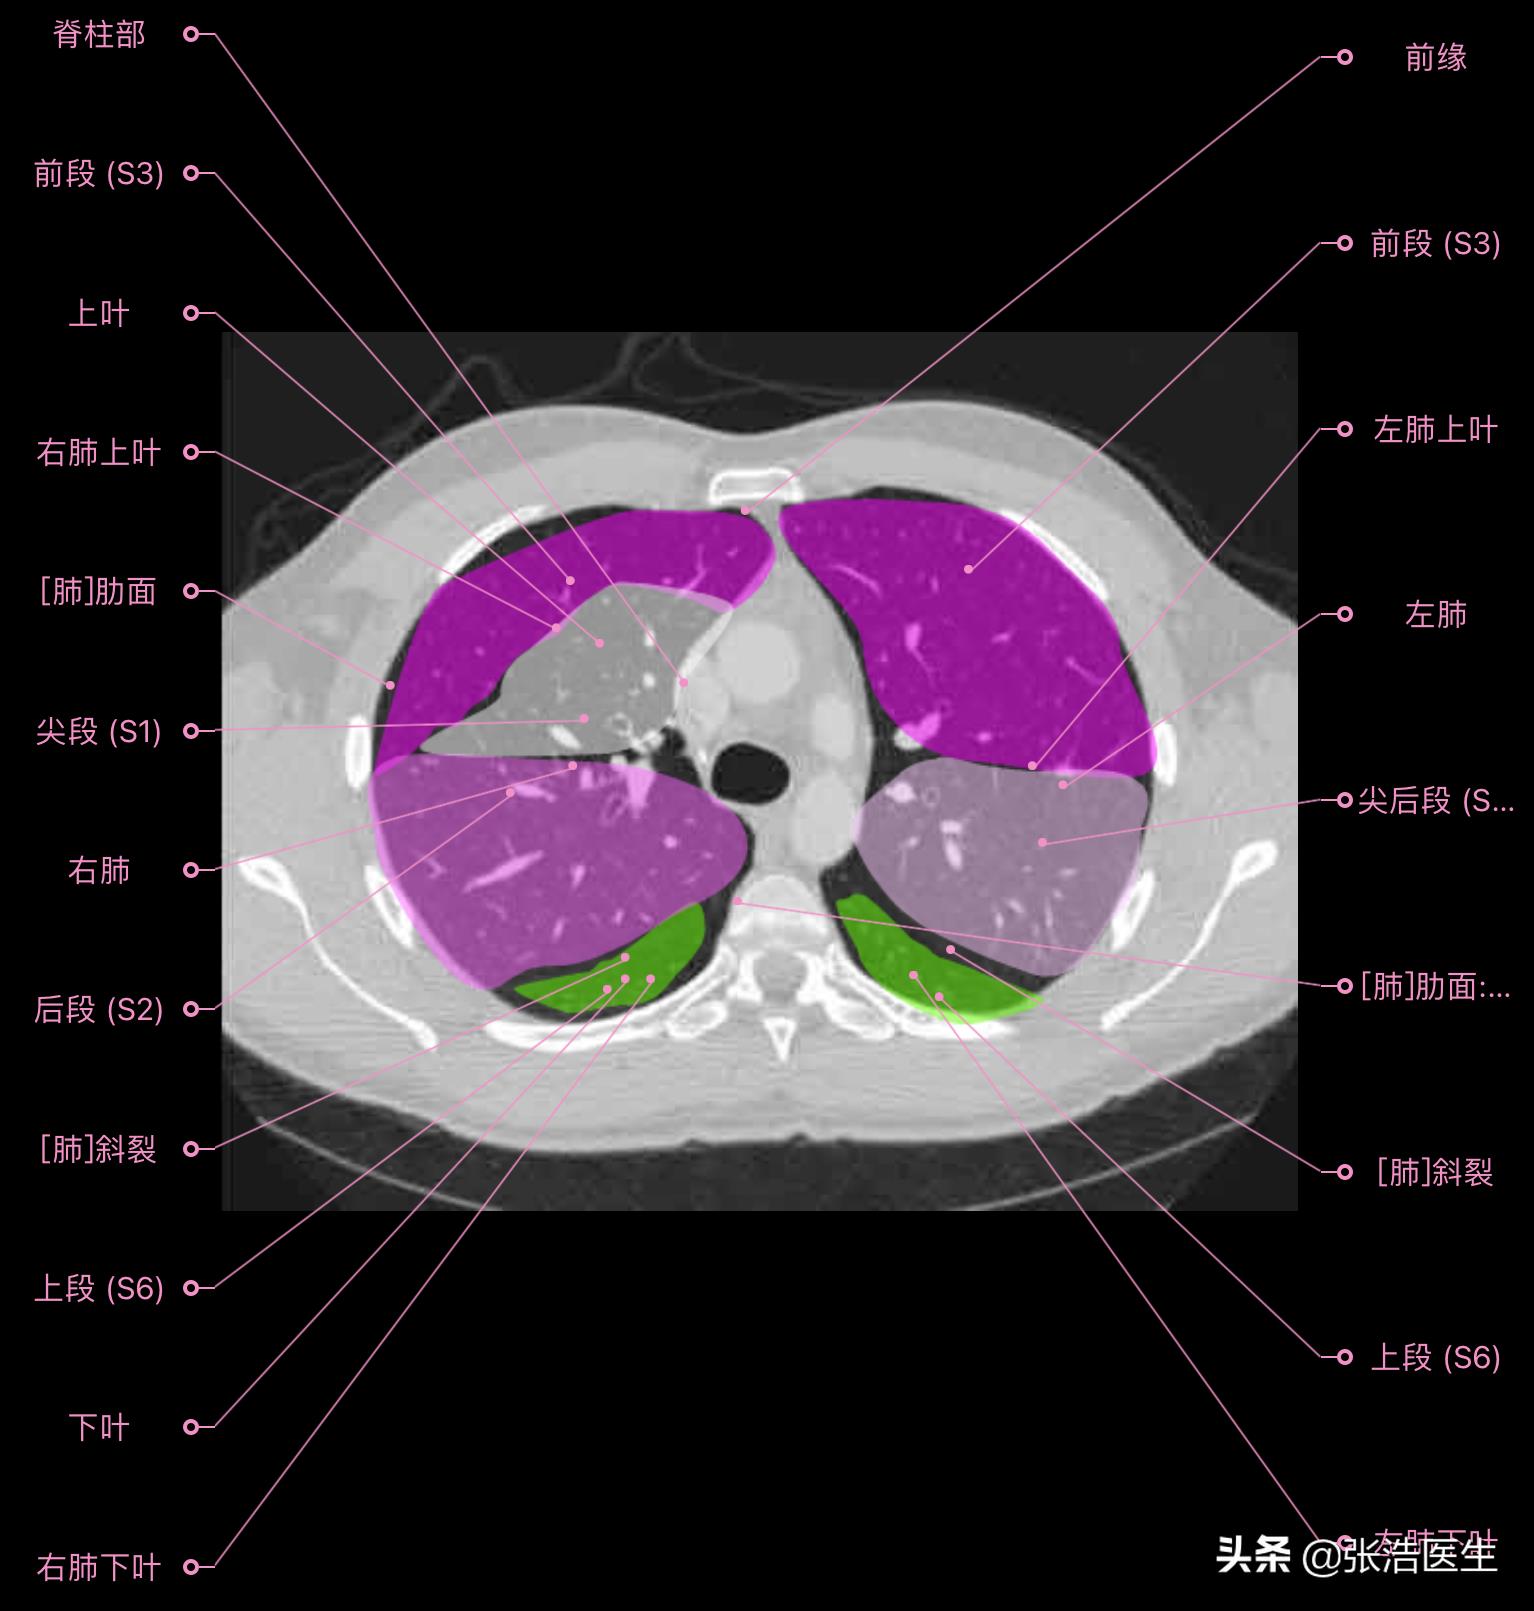

肺部CT横断面高清解剖图谱(图层4)